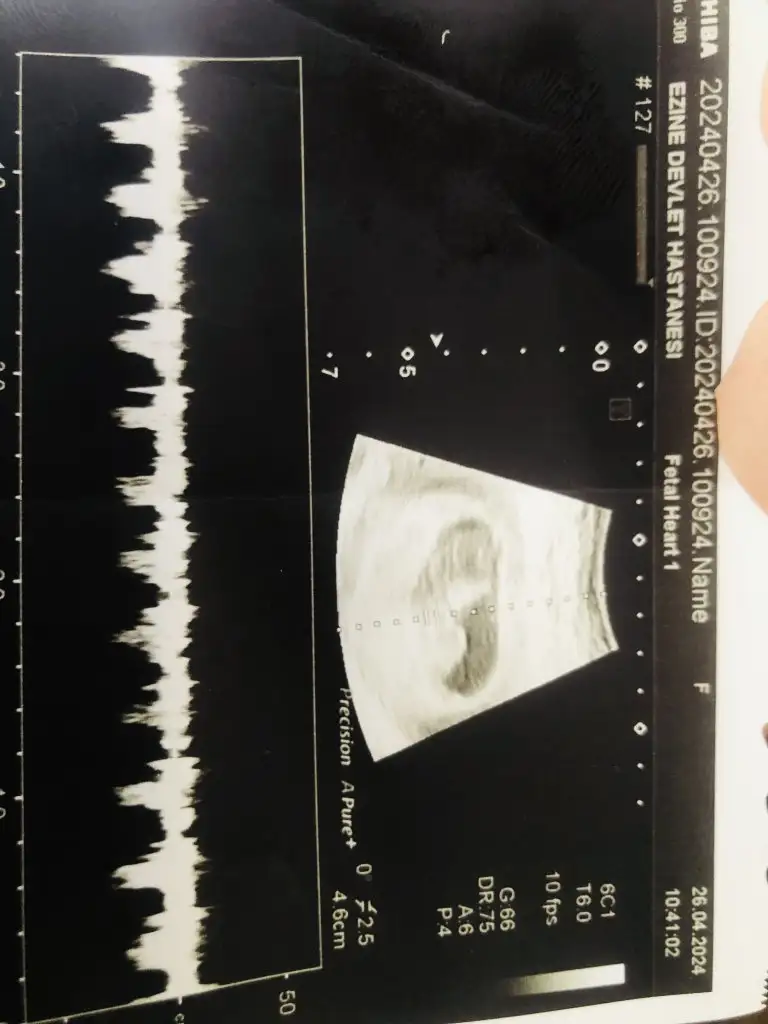

En zorlandığım üç tahmin listesine net girer bu bebiş annesi evirdim çevirdim yanıltmak da istemediğim için baya bı inceledim karından ultrason ise erkek.Son kararım bu arada ultrason kolunu saginda daha çok gezdirdi değil mi? O detayı Hatirliyosan daha net bişey soyleyebilirim.ama bence erkek

Ahahahahah ahh çocuğumm ne zorsunnn demekkk. Sanki sağ veya ortalardaydı bilemedimhatırlayamıyorum çokk teşekkür ederimmm mutlaka cinsiyet belli olunca yazacağım